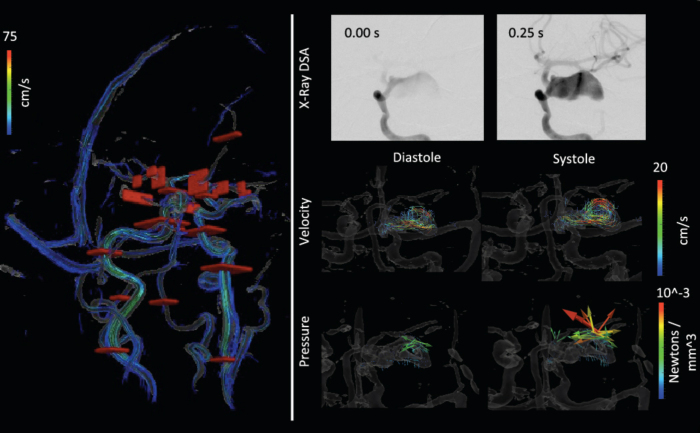

Fig. 2.

Cut planes used for flow volume calculations and temporal series of contrast inflow, and cine velocity and derived fluid force. Top: The cut planes (red surfaces) are shown in red over a rendering of the vascular structure and streamlines. Bottom: The upper row shows the contrast agent filling the fundus at 4 Hz; the middle row shows cine frames of the flow velocity; and the lower row shows the fluid force calculated from the Navier-Stokes equation at each pixel. The flow is observed to be higher toward the outer edgeof the aneurysm, while forces are higher in the middle and toward the end where the flow diverts backward.

The PC images highlighted only the region of flowing blood. The high-resolution PC MRI-derived velocity measurements confirmed that the velocities toward the periphery of the aneurysm were on the order of 5cm/s, whereas samples in the center of the fundus were around 1.5cm/s (Fig. 2). Figure 2 also shows the force vectors generated by the blood. These vectors are analogous to the pressure, though they show the direction of the fluid force. A higher pressure was observed in the aneurysm where the flow jet reversed or where the velocity was small.